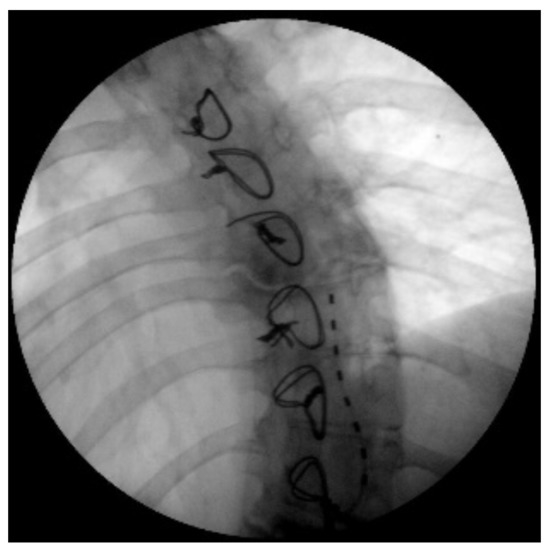

- -

2. First Clinical Evaluation and Background

3. Case Presentation